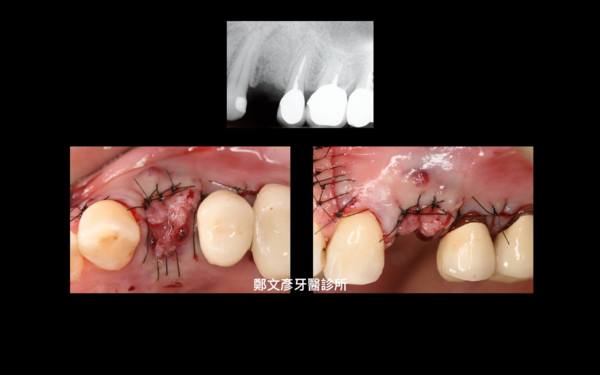

Role of granulation tissue in socket preservation

3. Role of granulation tissue in socket preservation